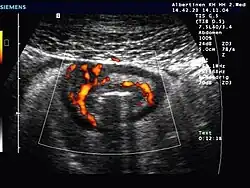

- Abdomensonographie (Ultraschall-Untersuchung des Bauches): Typisch ist die segmentale Verdickung der Darmmucosa (Schleimhautoberfläche).

Ultraschallbild bei M. Crohn mit Wandverdickung und verstärkter Durchblutung einer Dünndarmschlinge -